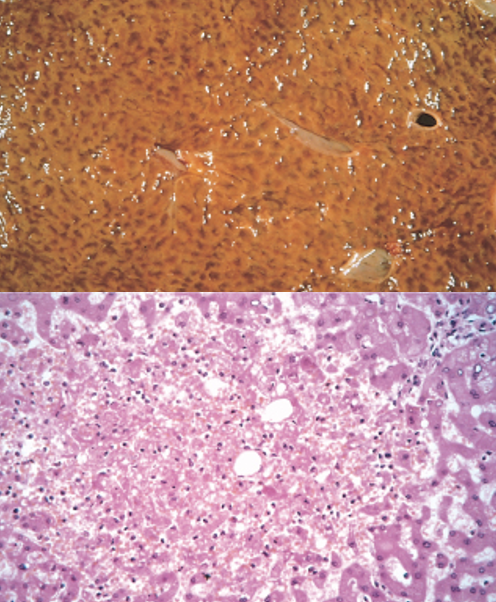

Liver with increased reticular pattern (chronic passive congestion or “nutmeg liver”)